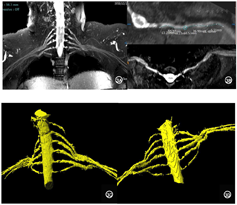

术后4个月复查臂丛神经MRI高分辨MRI平扫+增强显示:左侧C7椎间孔外神经干移位术后,吻合处神经显示良好(图4)。专科查体:左侧肢体肌力4级,肌张力正常,右侧近端肌力3级、远端肢体肌力0级,肌张力较前明显降低。右上肢Fugl-Meyer运动功能评分4分;华山分级:Ⅰ级;改良Ashworth分级:3级。患者言语不利较前明显改善,偶可发音清晰,左侧肩部、左手食指、中指无明显麻木疼痛。